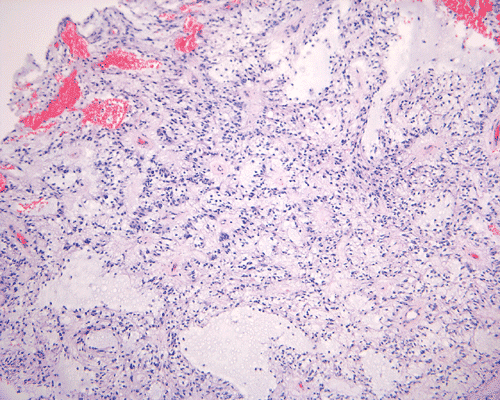

In a substantial amount of area, the tumor is composed of spindle cells with prominent perivascular arrangment and microcyst formation (Panel A and B). These vessels are surrounded by a thin rim of bipolar spindle cells (Panel C). The paucicellular perivascular mantle that is typical for ependymoma is absent in these perivascular arrangements. Adjacent to these perivascular arrangment is substantial amount of myxoid changes. On high-magnification, the tumor cells appear bland in histology, bioplar and spindle in shape, and admixed with a large amount of myxoid substance (Panel D and E). There is a lack of mitosis or significant pleomorphism. In some areas, the tumor is composed exclusively of spindle cells in a myxoid background with microcyst formation but without perivascular coronary arrangement of tumor cells (Panel F). It is not uncommon to observe areas with spindle cells clinging to the blood vessels (Panel G). In a minority of areas, there is increase in cellularity (Panel H). Some vessels seem to be composed of glomeruloids of blood vessels with plump endothelial cells (Panel I).

Histologically, the salient features of PMA are rather monotonous, small, spindle bipolar cells with angiocentric arrangement within a strikingly myxoid background. The myxoid basckground material is positive for Alcian blue but negative for PAS 1, 3,.  These features are well illustrated in our case. Occasional necrotic foci and mitotic figures can be present. Atypical mitotic figures and substantial nuclear pleomorphism should not be seen. Occasionally, the tumor cells infiltrate the surrounding non-neoplastic brain parenchyma but neither the histological feature nor radiological features would suggest a diffusely infiltrating astrocytoma. In contrast to pilocytic astrocytomas, PMAs do not possess a true alternating densely packed-loosely packed biphasic pattern, do not contain eosinophilic granular bodies or Rosenthal fibers 1, 4. Development of features that are seen in pilocytic astrocytomas such as the biphasic pattern and Rosenthal fibers have been described by Fernandez et al 4. These features are uncommon at the initial presentation but they can develop after chemotherapy. Although these features may suggest maturation of the tumor after chemotherapy, no association with improved prognosis has been described in the study by Fernandez et al 4. The angiocentric arrangement of tumor cells is another trap as it would suggest ependymoma. However, these arrangements are more irregular and fibrillar than the perivascular rosettes in ependymomas.